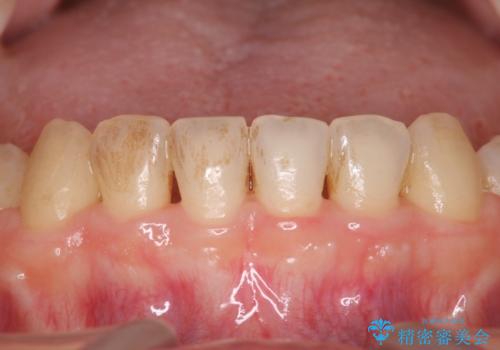

- メンテナンスの際に歯のステインが気になるということで今回はエアフローの機械を使用したクリーニングを行いました。

ステインが付着したままだと歯の表面がざらつき、普段のブラッシング時などに汚れが落ちにくくなります。定期的なメンテナンスの際にPMTC、エアフローを取り入れることをおすすめしております。